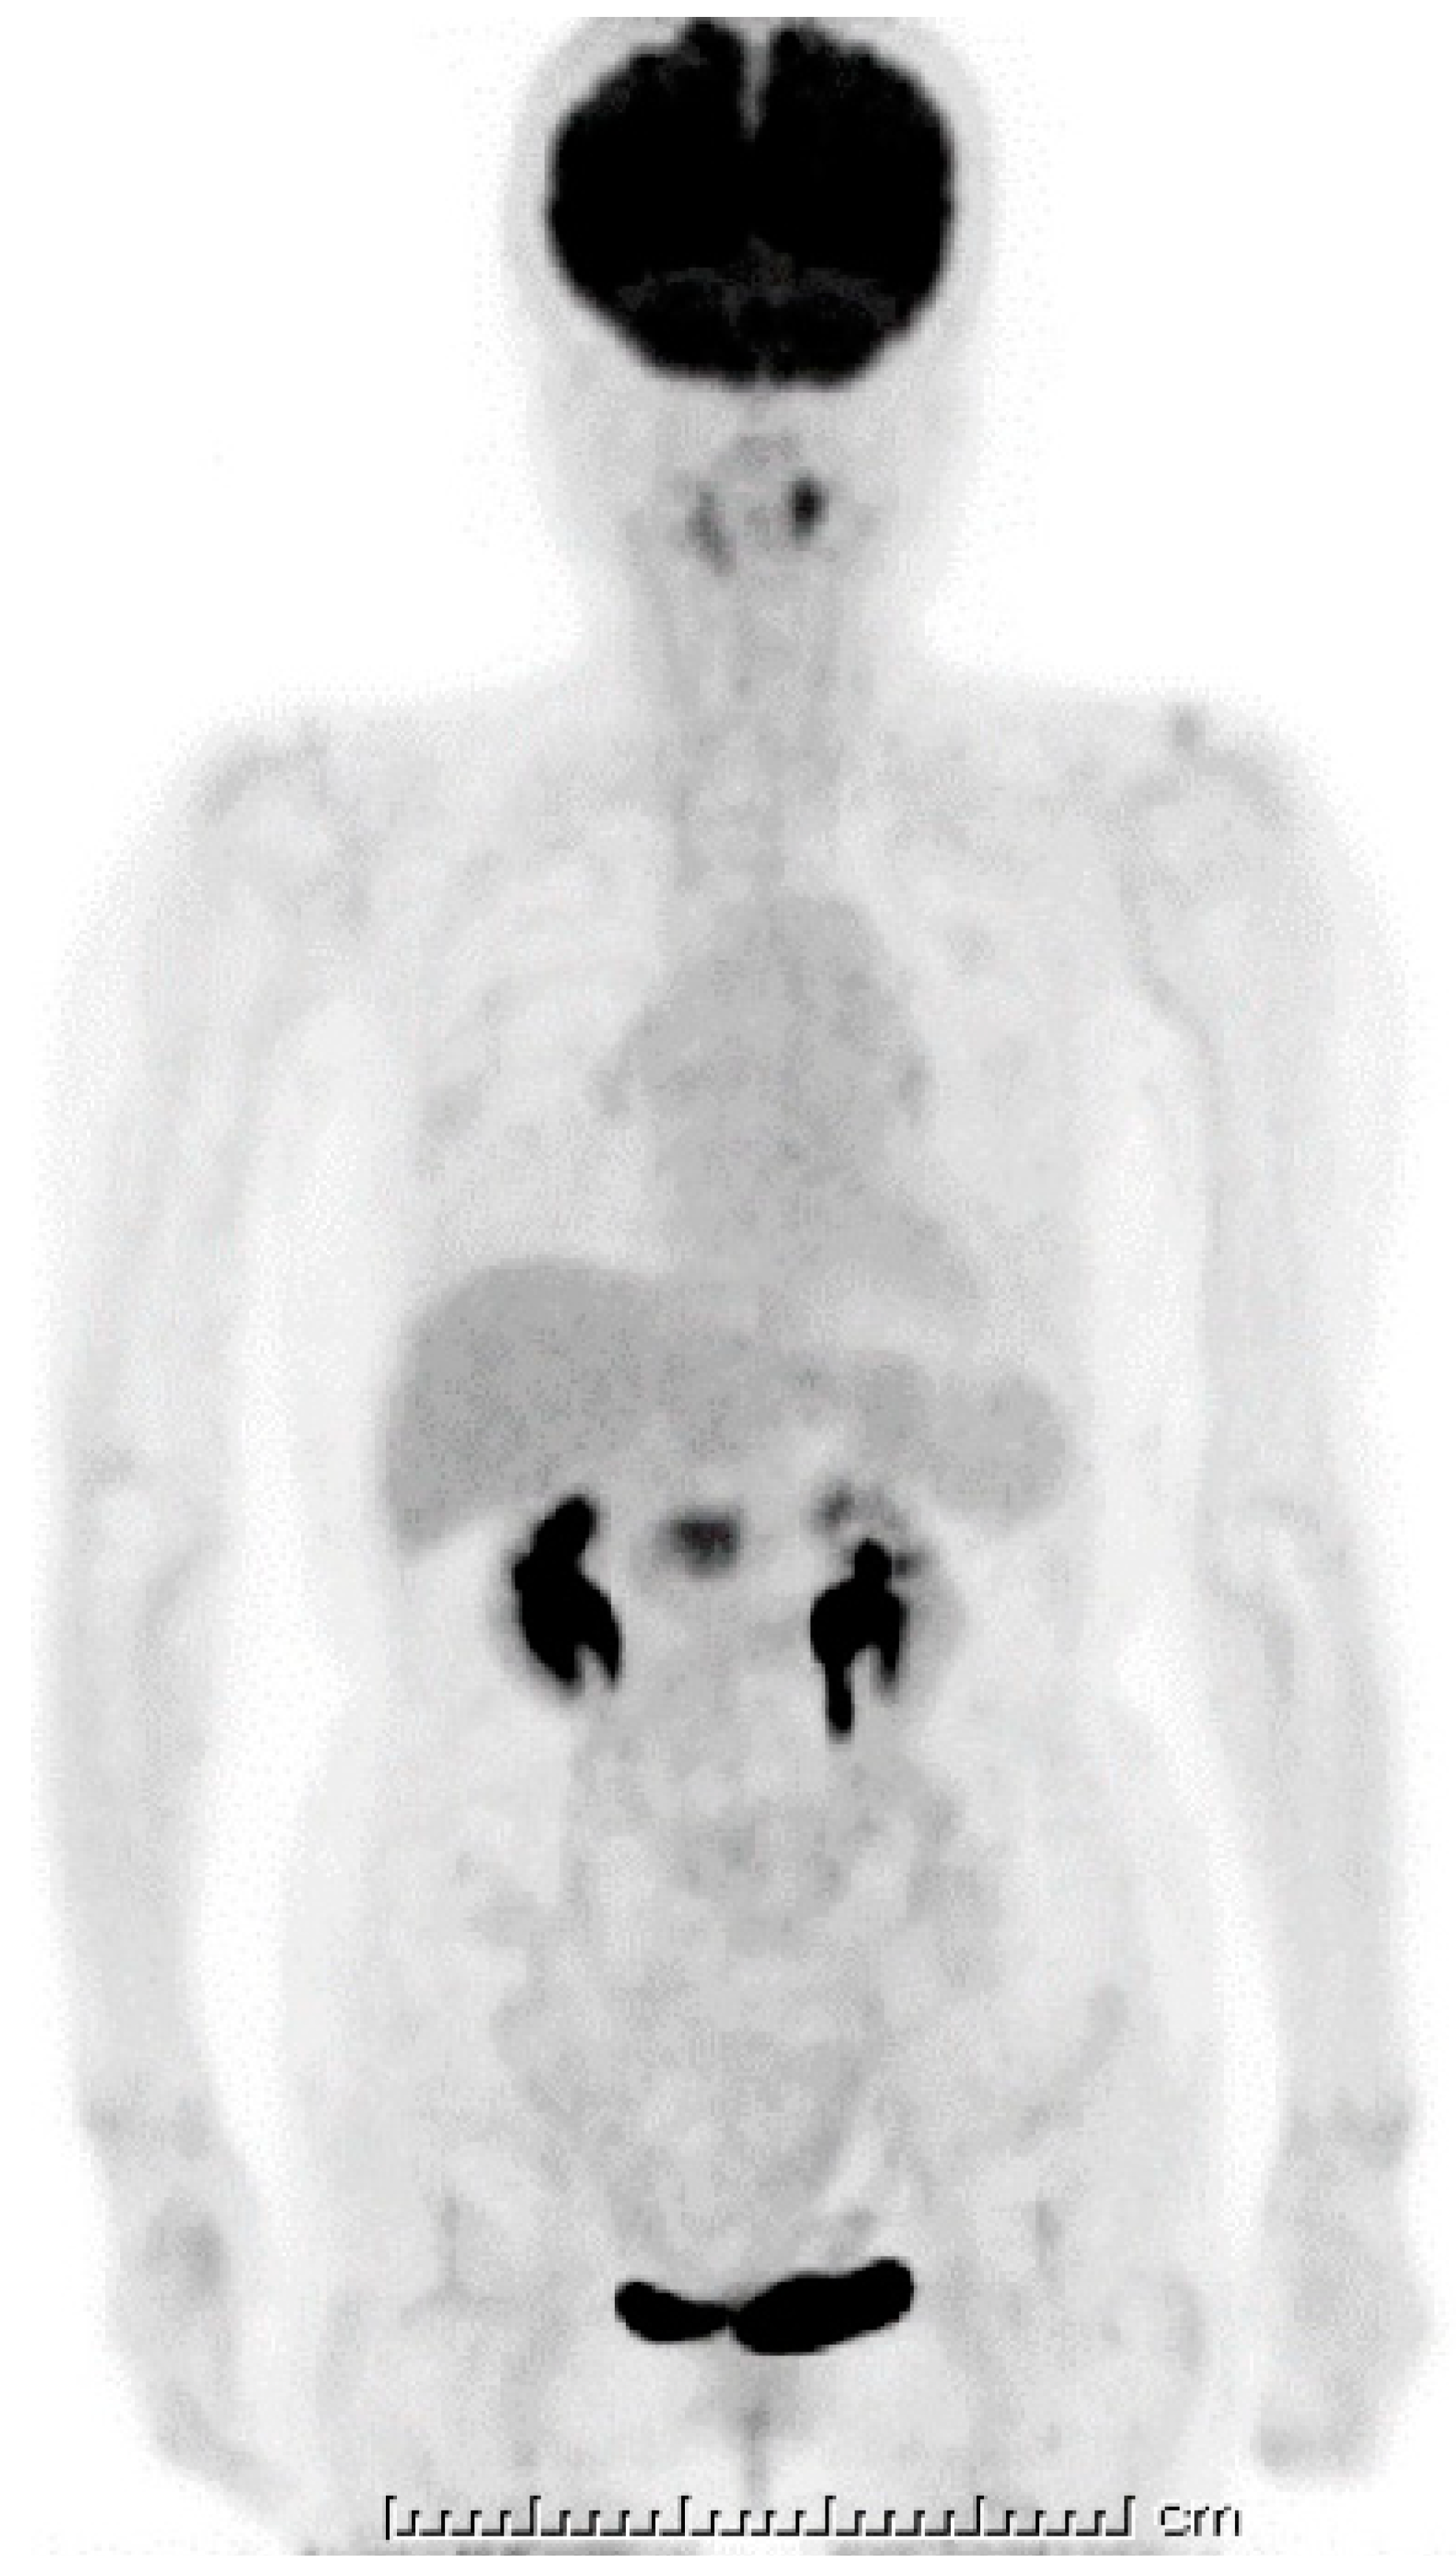

Figure 5.

18F-fluorodeoxyglucose positron emission tomography (FDG-PET). A strong uptake of FDG was visible at the pancreas head (SUVmax: 6.95); however, this looked smaller when compared with the initial computed tomography (CT) image. The one unit of under bar is indicating 1cm and total bar length is 25 cm.

Ten days after FNAB, positron emission tomography showed abnormal 18F-fluorodeoxyglucose uptake (SUVmax: 6.95); however, the pancreatic lesion seemed to have shrunk to 2.5 cm in size (Figure 5). Magnetic resonance imaging (MRI) demonstrated an obviously minimized tumorous lesion at the pancreas head (Figure 6). The mass lesion was visible as an iso-intensity signal in a T1-weighted image and as a faintly low-intensity signal in a T2-weighted image, while it was ill enhanced in an EOB image and the signal was heterogeneously repressed in a diffusion-weighted image. A subsequent CT, conducted one month after the FNAB, revealed further minimization of the pancreatic mass (Figure 1c,d). The images obtained in the next two months showed that the tumor had almost vanished. The tumor was no longer visible at the sixth month. During the post-diagnosis course, no medication was administered other than regularly taken hypotensive drugs. A written informed consent was obtained from the patient.